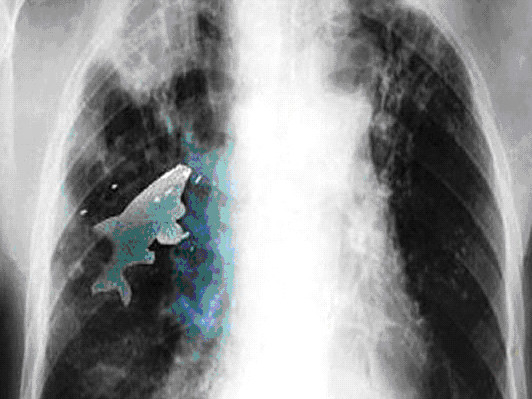

| Con cá trong phổi Anil (Ảnh: The Sun). |

Các bác sĩ liền chụp X- quang phổi và thật bàng hoàng khi thấy rõ con cá đang nằm gọn trong buồng phổi trái của Anil. Họ quyết định phẫu thuật khẩn cấp.

Bác sĩ Pramod Jhawar nói: “Con cá vẫn còn sống cho đến khi chúng tôi tiến hành nội soi phế quản của cậu bé. Sự xuất hiện của cá cản trở chức năng hoạt động bình thường của đường dẫn khí và hai lá phổi, dẫn đến tình trạng thiếu oxy trong máu".

"Đây là lần đầu tiên chúng tôi gặp phải trường hợp này trong suốt 20 năm làm việc", bác sĩ Pramod Jhawar nói thêm.